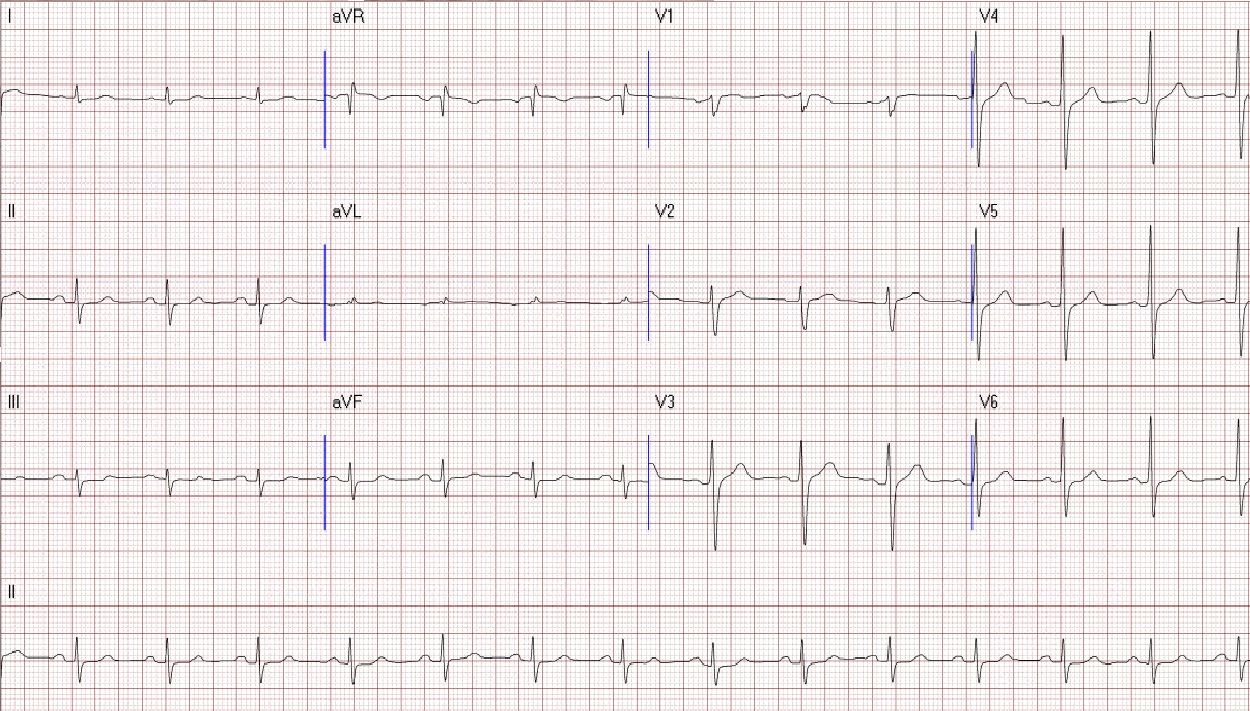

A 64-year-old male with chest pain and tightness during exertion for 2 months, relieved by rest. Past history: type 2 diabetes, hypertension. No smoking or family history. Sinus rhythm EKG. Clear lungs, no cardiomegaly on chest x-ray. Angiography: LM bifurcation (Medina 1,1,1), diffuse LAD, severe LCX AS, 95% eccentric LAD, long RCA CTO. Syntax score 25, EuroScore II 0.84%. CABG advised, patient sought second opinion here.